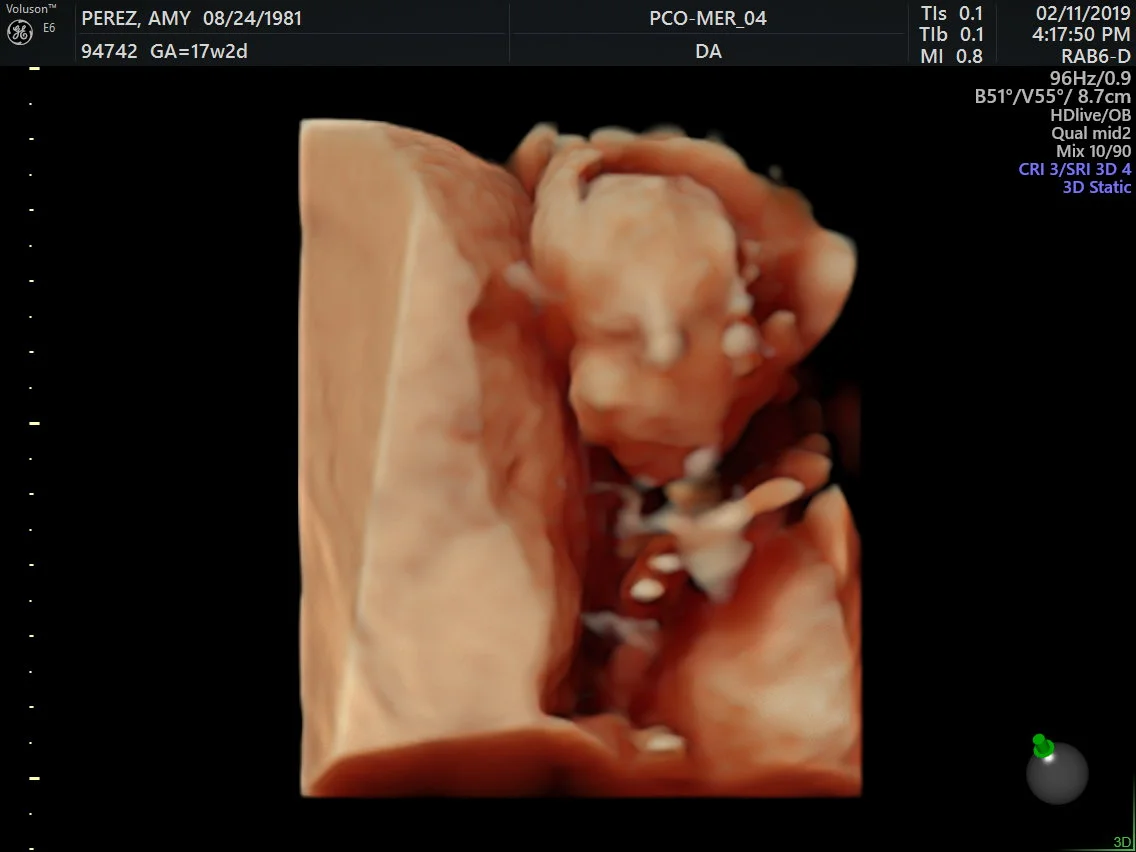

SONOGRAM #2

IT’S A GIRL!!! We had our 16 week sonogram appointment earlier this week and everything went very good. There is no real meaning or story behind her first name Pressa but it was just something we thought of a couple years ago. Her middle name Eve is a shortened version of Amy’s late brother’s middle name Everette.